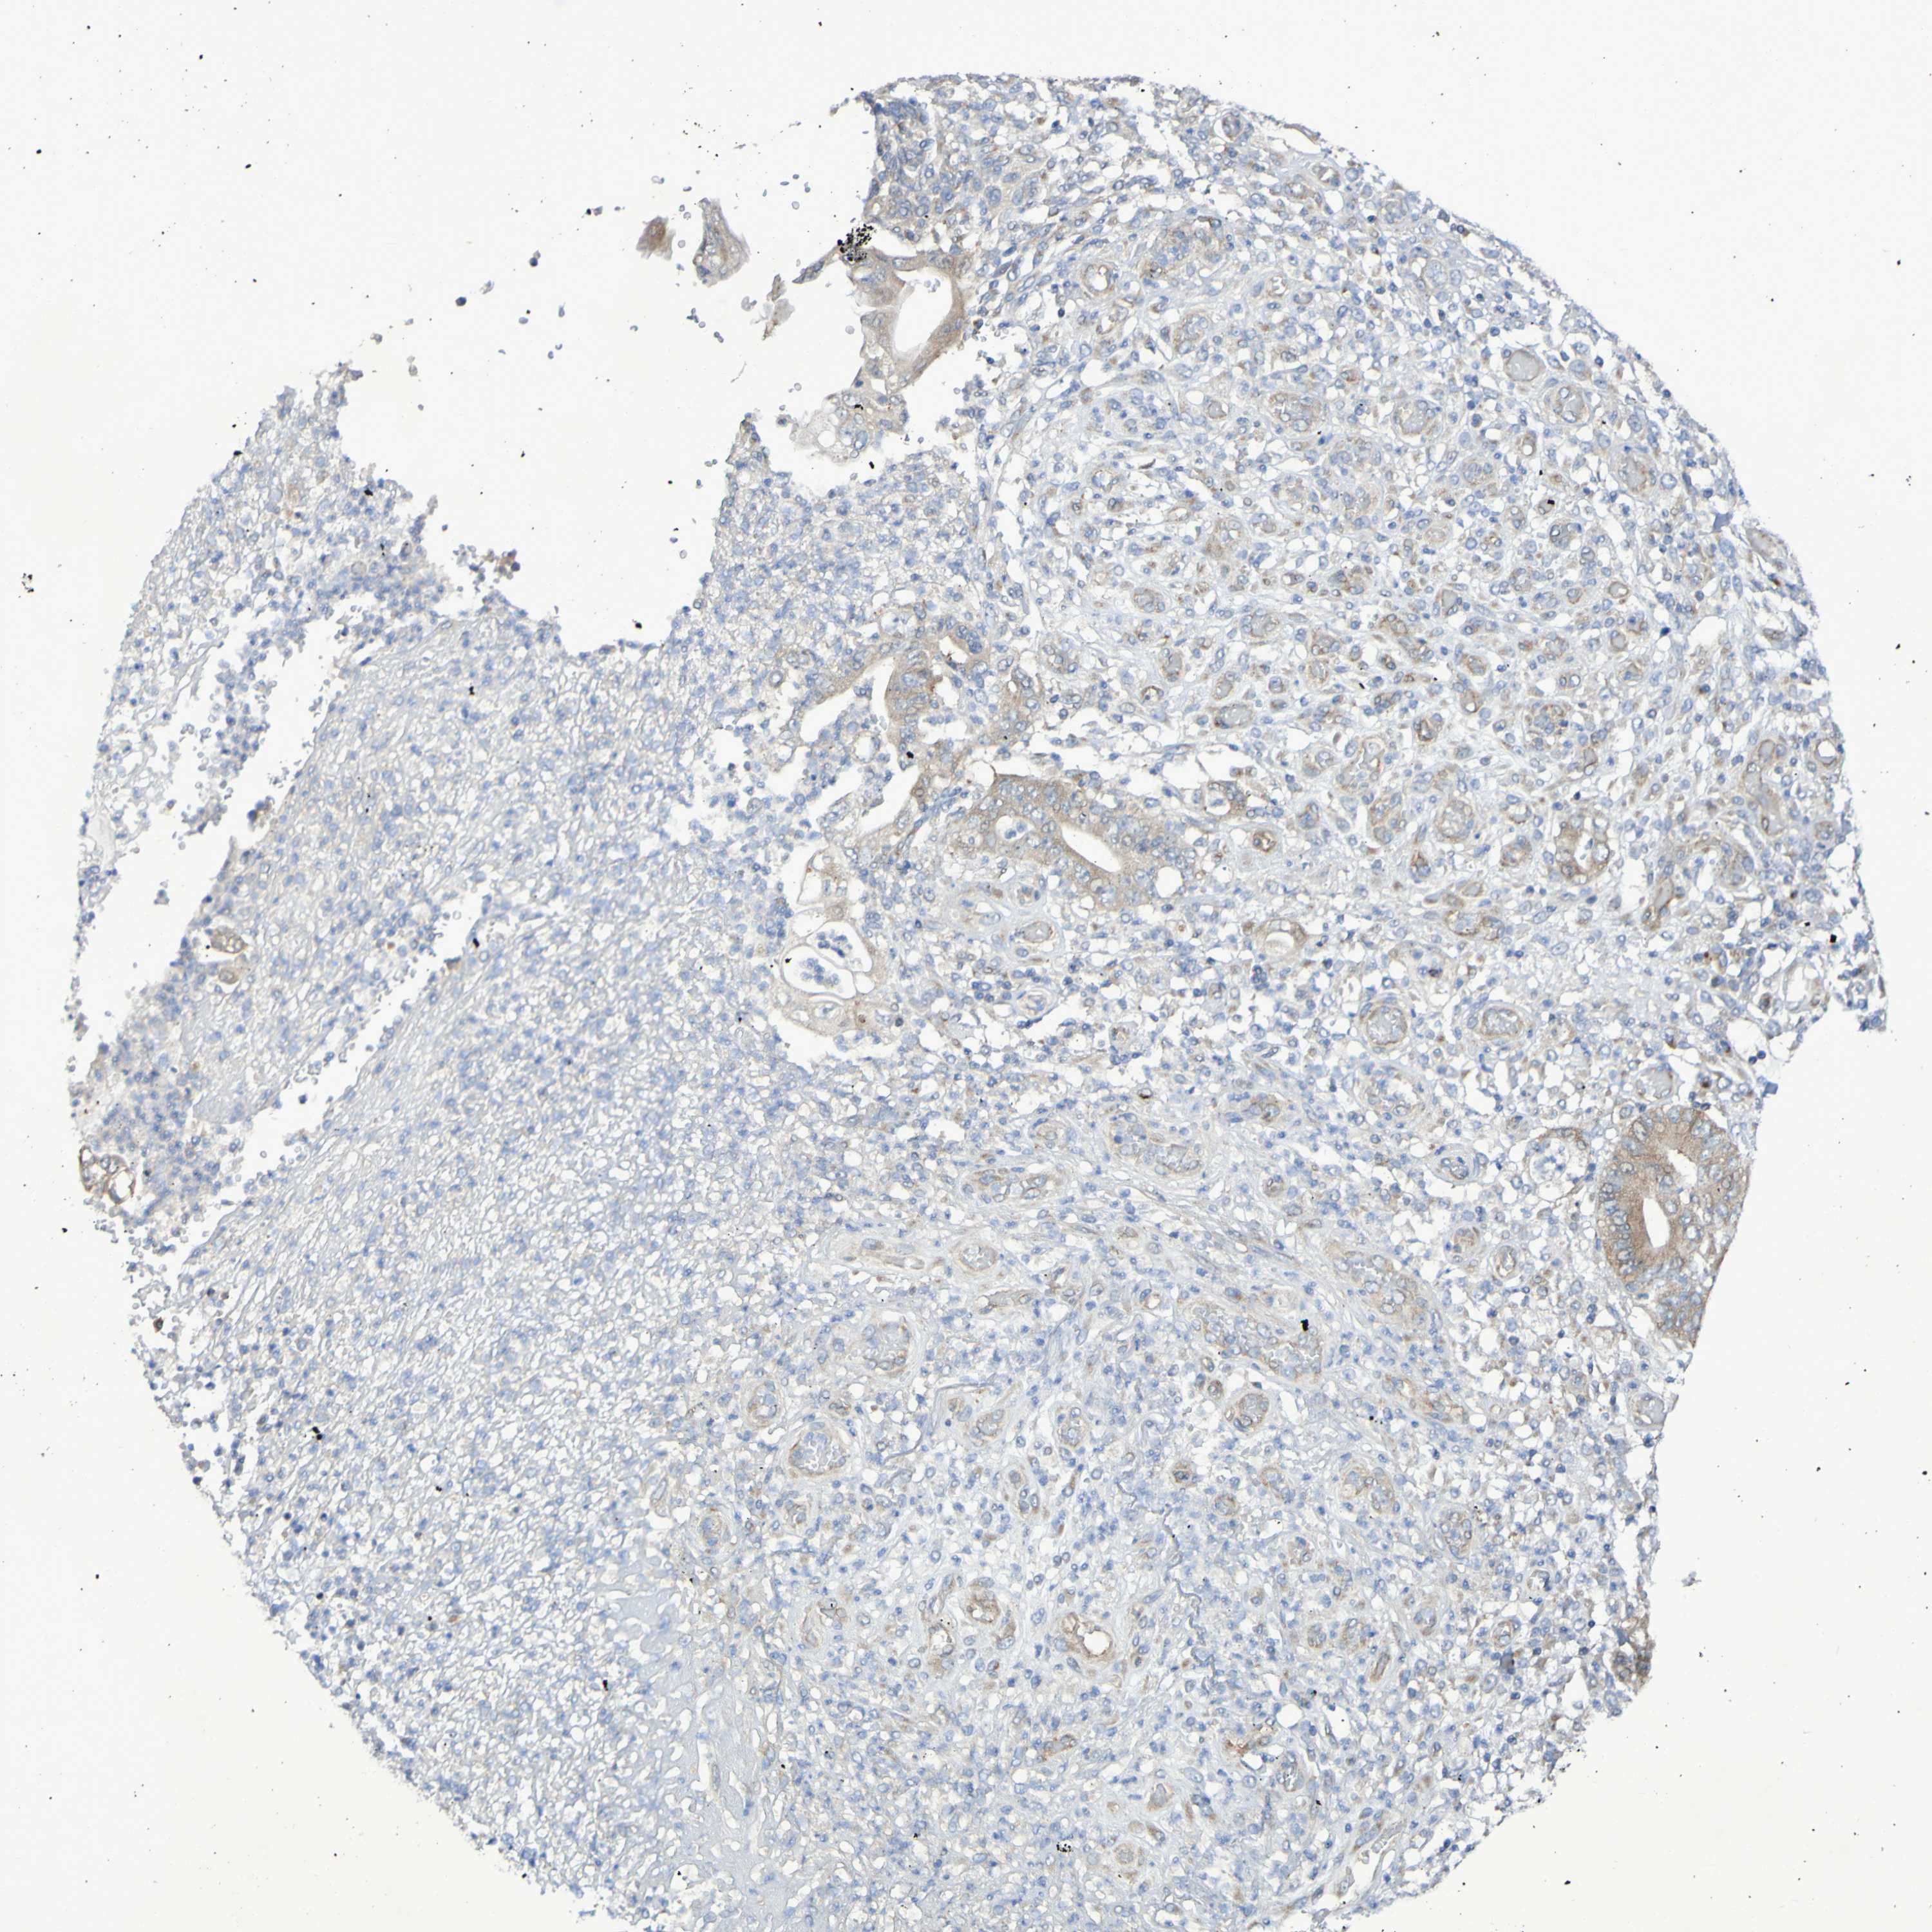

STOMACH CANCER - Protein expressioni

A mouse-over function shows sample information and annotation data. Click on an image to view it in a full screen mode. Samples can be filtered based on level of antibody staining by selecting one or several of the following categories: high, medium, low and not detected. The assay and annotation is described here.

Antibody stainingi

Antibody staining in the annotated cell types in the current human tissue is reported as not detected, low, medium, or high, based on conventional immunohistochemistry profiling in selected tissues. This score is based on the combination of the staining intensity and fraction of stained cells.

Each image is clickable and will lead to virtual microscopy that enables deeper exploration of all samples and also displays staining intensity scores, fraction scores and subcellular localization as well as patient and tissue information for each sample.

Antibody HPA012165

Staining

High

Medium

Low

Not detected

Intensity

Strong

Moderate

Weak

Negative

Quantity

>75%

75%-25%

<25%

None

Location

Nuclear

Cytoplasmic/membranous

Cytoplasmic/membranous,nuclear

Adenocarcinoma, NOS

Adenocarcinoma, High grade